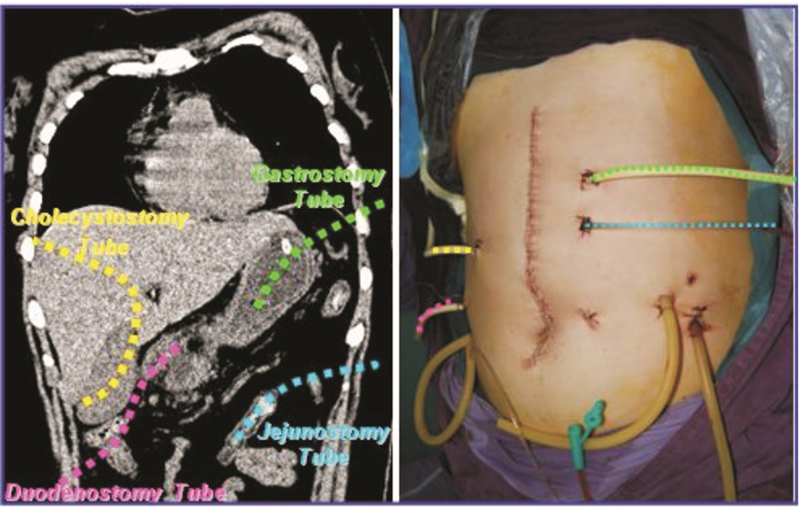

经适当补液、抑酸、抑酶及抗炎治疗后,患者病情趋于稳定,但胰腺及胰周组织病理变化进展迅速(图 1)。2周后,CT提示胰头及胰尾部大面积坏死,胰周大量积液伴右结肠旁沟、脾窝、肠系膜根部有气体分布。同时患者出现持续高热,广谱抗生素不能控制。临床考虑患者已处于胰腺感染性坏死期,遂于发病第26天行手术治疗。术中发现胰周及结肠旁沟大量脓血性液体积聚,胰腺水肿明显并伴有大面积脂肪组织坏死。而且胃小弯及十二指肠降部发现两个穿孔(图 2),同时远端胃被大量纤维组织包裹,遂给予充分暴露清创后单纯缝合各穿孔,并分别进行胃、胆囊、十二指肠及空肠造口置管以达到胰周减压及实施肠内营养的目的(图 3)。术后,在有效的腹外脓腔引流及肠内营养支持下,患者病情逐步好转,胰周及后腹膜脓腔逐渐变小并消失(图 1)。但是术后1个月,患者食管起始部及胃流出道狭窄。暂时给予患者全肠内营养并等待消化道重建术(见图 4)。

在胃(绿色)、胆囊(黄色)、十二指肠(粉色) 及空肠(蓝 色)行造口置管以达胰腺减压及实施肠内营养目的 图 3 胃、十二指肠、空肠及胆囊造瘘管的放置位置示意图